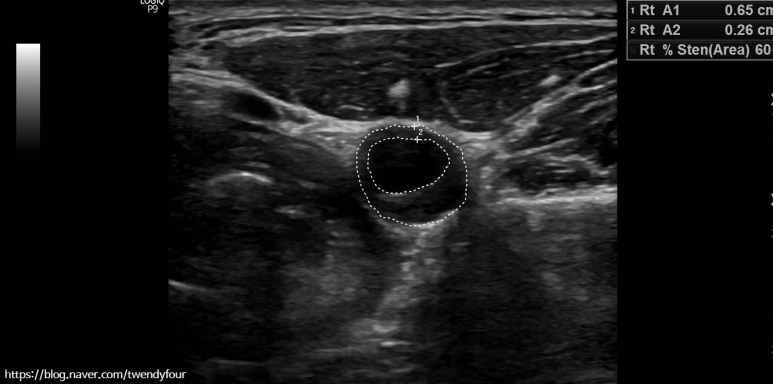

45세 남성, 경동맥 혈관 벽이 60% 좁아져 있다.

만약 혈관 벽이 두꺼워지고 혈관 벽이 좁아졌다면 얼마나 두꺼워졌는지 퍼센트로 경동맥 협착증을 확인합니다.정밀경동맥 초음파 검사는 경동맥 혈관 벽이 50% 이상 두꺼워진 분에게 더 깊이 들어갑니다.

경동맥 중의 내경동맥, 머리에 혈관의 정밀 경동맥 초음파 검사 사진입니다.